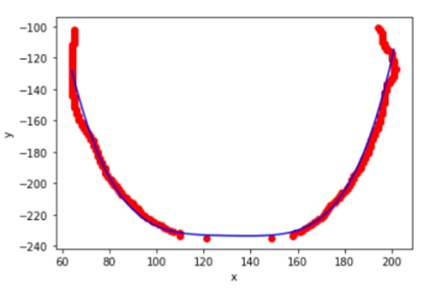

对下0.75舌位标记像素点进行舌体轮廓的多项式曲线拟合。由于分析的是曲线的“胖瘦”,因此多项式曲线的奇数次项影响较小,且项数较大较好。权衡模型的运行效率,中e诊采用4次项多项式曲线拟合。进行多张图片拟合的确定系数(R-square=SSR/SST)为0.82~0.95,说明4次多项式曲线拟合效果较好。舌体轮廓4次多项式拟合示意图如下:

将得到4次多项式拟合曲线系数代入如下公式,计算胖瘦指数。通过胖瘦指数来判断用户舌体的胖瘦。

其中a4为四次项系数,a2为二次项系数。

胖瘦值数越大说明舌体越宽大,胖瘦指数越小说明舌体越瘦小;胖瘦指数位于4.3-7.8范围内是正常舌,小于4.3是瘦小舌,大于7.8是肥大舌。